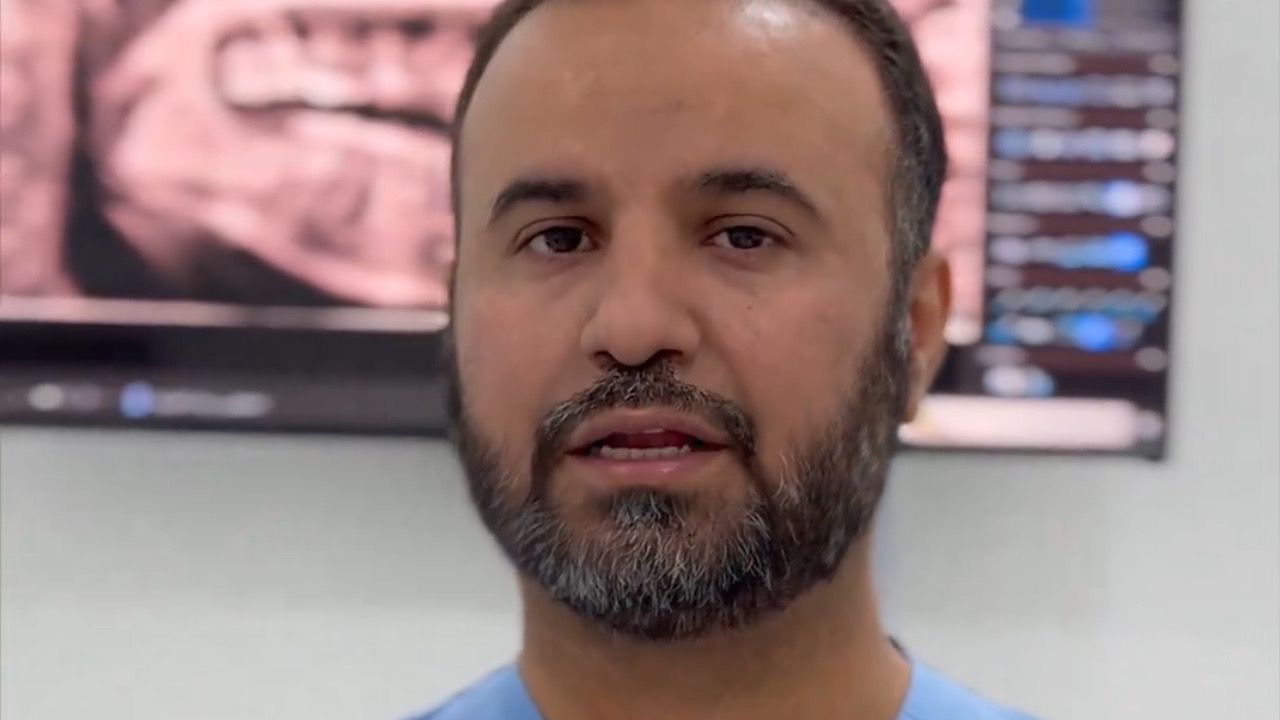

استشاري يحذر من إهمال الفم والأسنان في رمضان ..فيديو

استشاري يقدم نصائح للحفاظ على صحة الأسنان